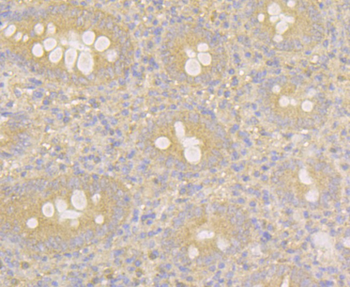

- PPM1D Rabbit Polyclonal Antibody [orb704535]Featured

IF, IHC-Fr, IHC-P

Human, Mouse, Rat

Mouse, Rat

Rabbit

Polyclonal

Unconjugated

100 μl, 50 μl, 200 μl - HSC70 Mouse Monoclonal Antibody [orb704174]Featured